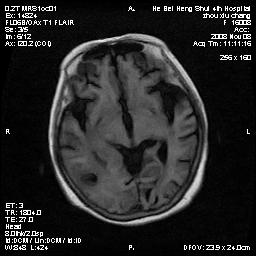

标题: MRI1883:女67岁,半年前曾患脑梗塞,治疗后好转,近3各月精 [打印本页]

标题: MRI1883:女67岁,半年前曾患脑梗塞,治疗后好转,近3各月精

女67岁,半年前曾患脑梗塞,治疗后好转,近3各月精神恍惚。

形态及整体病灶看起来首先考虑转移瘤或淋巴瘤,但奇怪的是多个病灶周围均未见显著的水肿区,这不符合这两个肿瘤的特点,结合ct表现及患者病史有个人考虑是否有皮层下动脉硬化性脑病伴多发胶质增生可能.